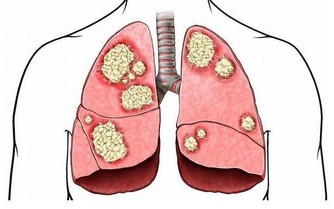

這個病名很專業,可能很多非血液科的醫生都沒聽到過。說直白點,就是患者的造血幹細胞惡性克隆,導致無效造血。白血病,我們通常稱之為血癌,骨髓增生異常綜合征其實也是一種血液腫瘤。這種病預後很差,有30%左右的患者會發展為白血病。

研究認為,苯是染髮劑中最基本的化學物質,對造血系統具有強烈毒性。染髮劑使用一個階段后,苯會沿頭髮浸入頭皮毛細血管,破壞造血系統,引起頭暈、乏力、皮下、內臟和腦出血,更加嚴重的是誘發癌症。近年來,醫學界常使用「染髮白血病」這個名詞,表明了染髮與白血病的關係。

美國和加拿大一項研究調查了766名成人白血病患者和623名沒有得過白血病的健康人,與沒有使用染髮劑的人比較,使用持久性染髮劑和半持久性染髮劑者患急性白血病的危險性較高。